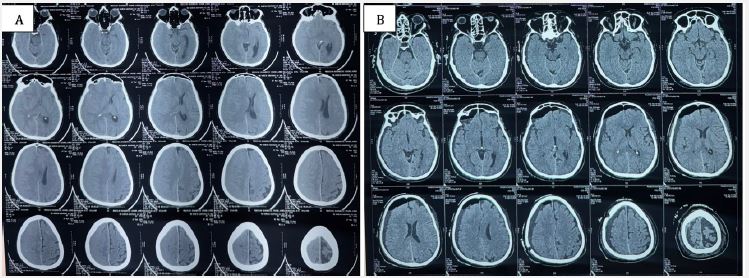

An NCCT head revealed a subacute SDH along the right fronto-parieto-temporal convexity with effacement of adjacent sulcal spaces, mass effect on the right lateral ventricle, and significant midline shift (Figure 1A). He was taken up for right-sided burr hole craniotomy and evacuation of hematoma under general anesthesia. Postoperatively, he showed marked improvement in sensorium and resolution of headache, with improvement in left-sided power to near normal.

Given his recent cardiac intervention, antiplatelet therapy was restarted postoperatively after discussion with cardiology. The patient was discharged with an intact sensorium and advised follow-up (Figure 1B).